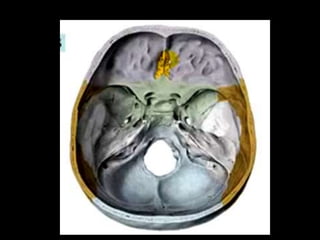

BASE DE CRANEO

Endocraneal

• Fosa craneal anterior

• Fosa craneal media

• Fosa craneal posterior

BASE

(ENDOCRANEAL)

Limites

• Una línea imaginaria que pasa por el borde

posterior de las alas menores del

esfenoides, apófisis clinoides anteriores,

borde anterior de la silla turca, hasta el final

del lado opuesto

• Una línea que pasa por el borde superior

del peñasco del temporal, apófisis clinoides

posteriores, borde posterior de la silla turca

• Fosa Cerebral Anterior: cresta frontal, apófisis

cristagalli, agujero ciego, lámina cribosa, porción

orbitaria del frontal, alas menores, apófisis clinoides

anteriores

• Fosa Cerebral Media: Canal óptico, conducto óptico,

agujeros ópticos, silla turca, agujero redondo mayor,

agujero redondo menor, agujero oval, agujero rasgado

anterior, hendidura esfenoidal

• Fosa Cerebral Posterior: Agujero Rasgado Posterior,

apófisis clinoides posteriores, surco del seno petroso

superior, conducto auditivo interno, agujero magno,

apófisis basilar, protuberancia occipital interna